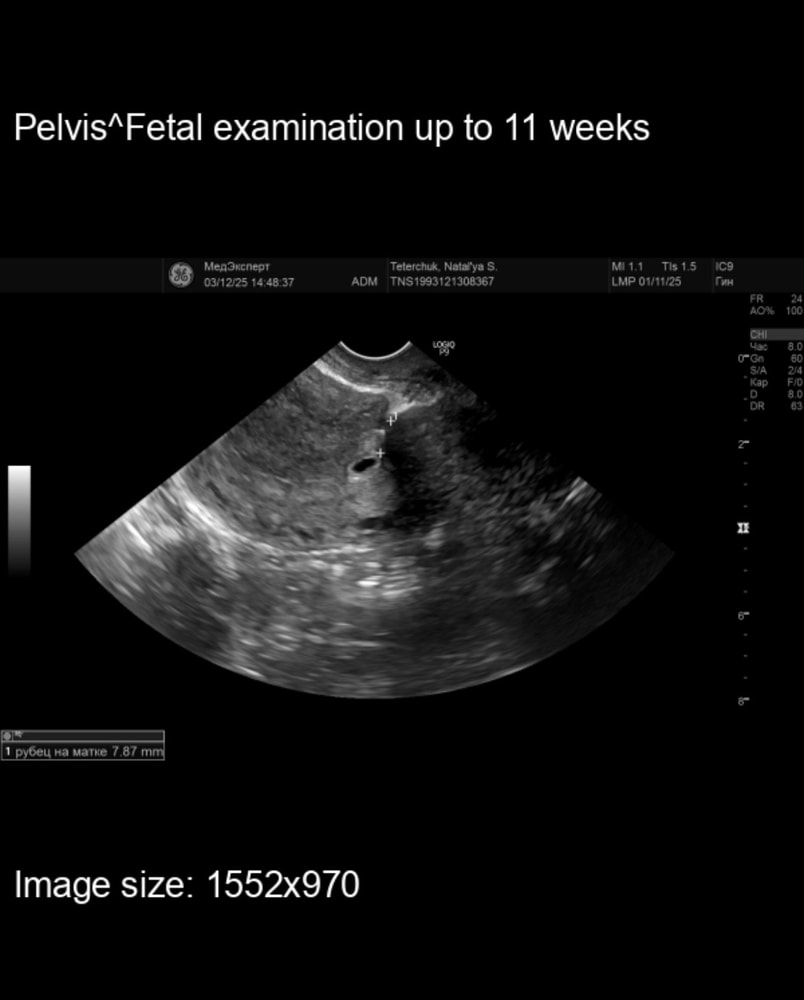

Добрый вечер. Сегодня у меня 4 Нед 4 дня,сходила я на узи. Эмоций просто через край. Во первых со мной на разговаривал специалист,я задала всего лишь один вопрос «все ли нормально ,или я рано пришла?» на что мне ответили «не мешайте», потом сказали что есть желтое тело и не видно плодного яйца ни где. А когда я приехала домой и посмотрела заключение и снимки ,оказалось у меня ниша появилась ,которой не было в течении 3.5 лет. (И рубец я в начале ноября проверяла)

ЛерЧик, посмотри фото ,на что это похоже ? Я просто не знаю. Самое интересное почему она мне не сказала ни чего словами про нишу. А лишь заключение ,возможно она перепутала.

Юля, а откуда появилась ниша,если ее не было. Это главный вопрос

Юлия, это типа дыры (кармана) на рубце